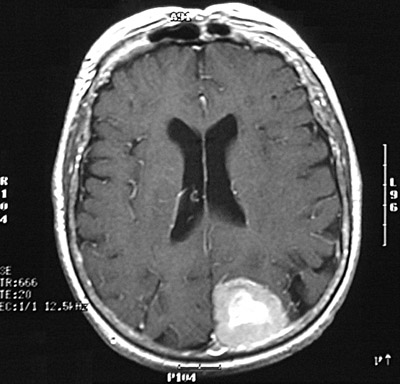

Here is a fast spin echo T2 weighted MRI scan in axial view that demonstrates bright central enhancement of a meningioma posteriorly near the falx.